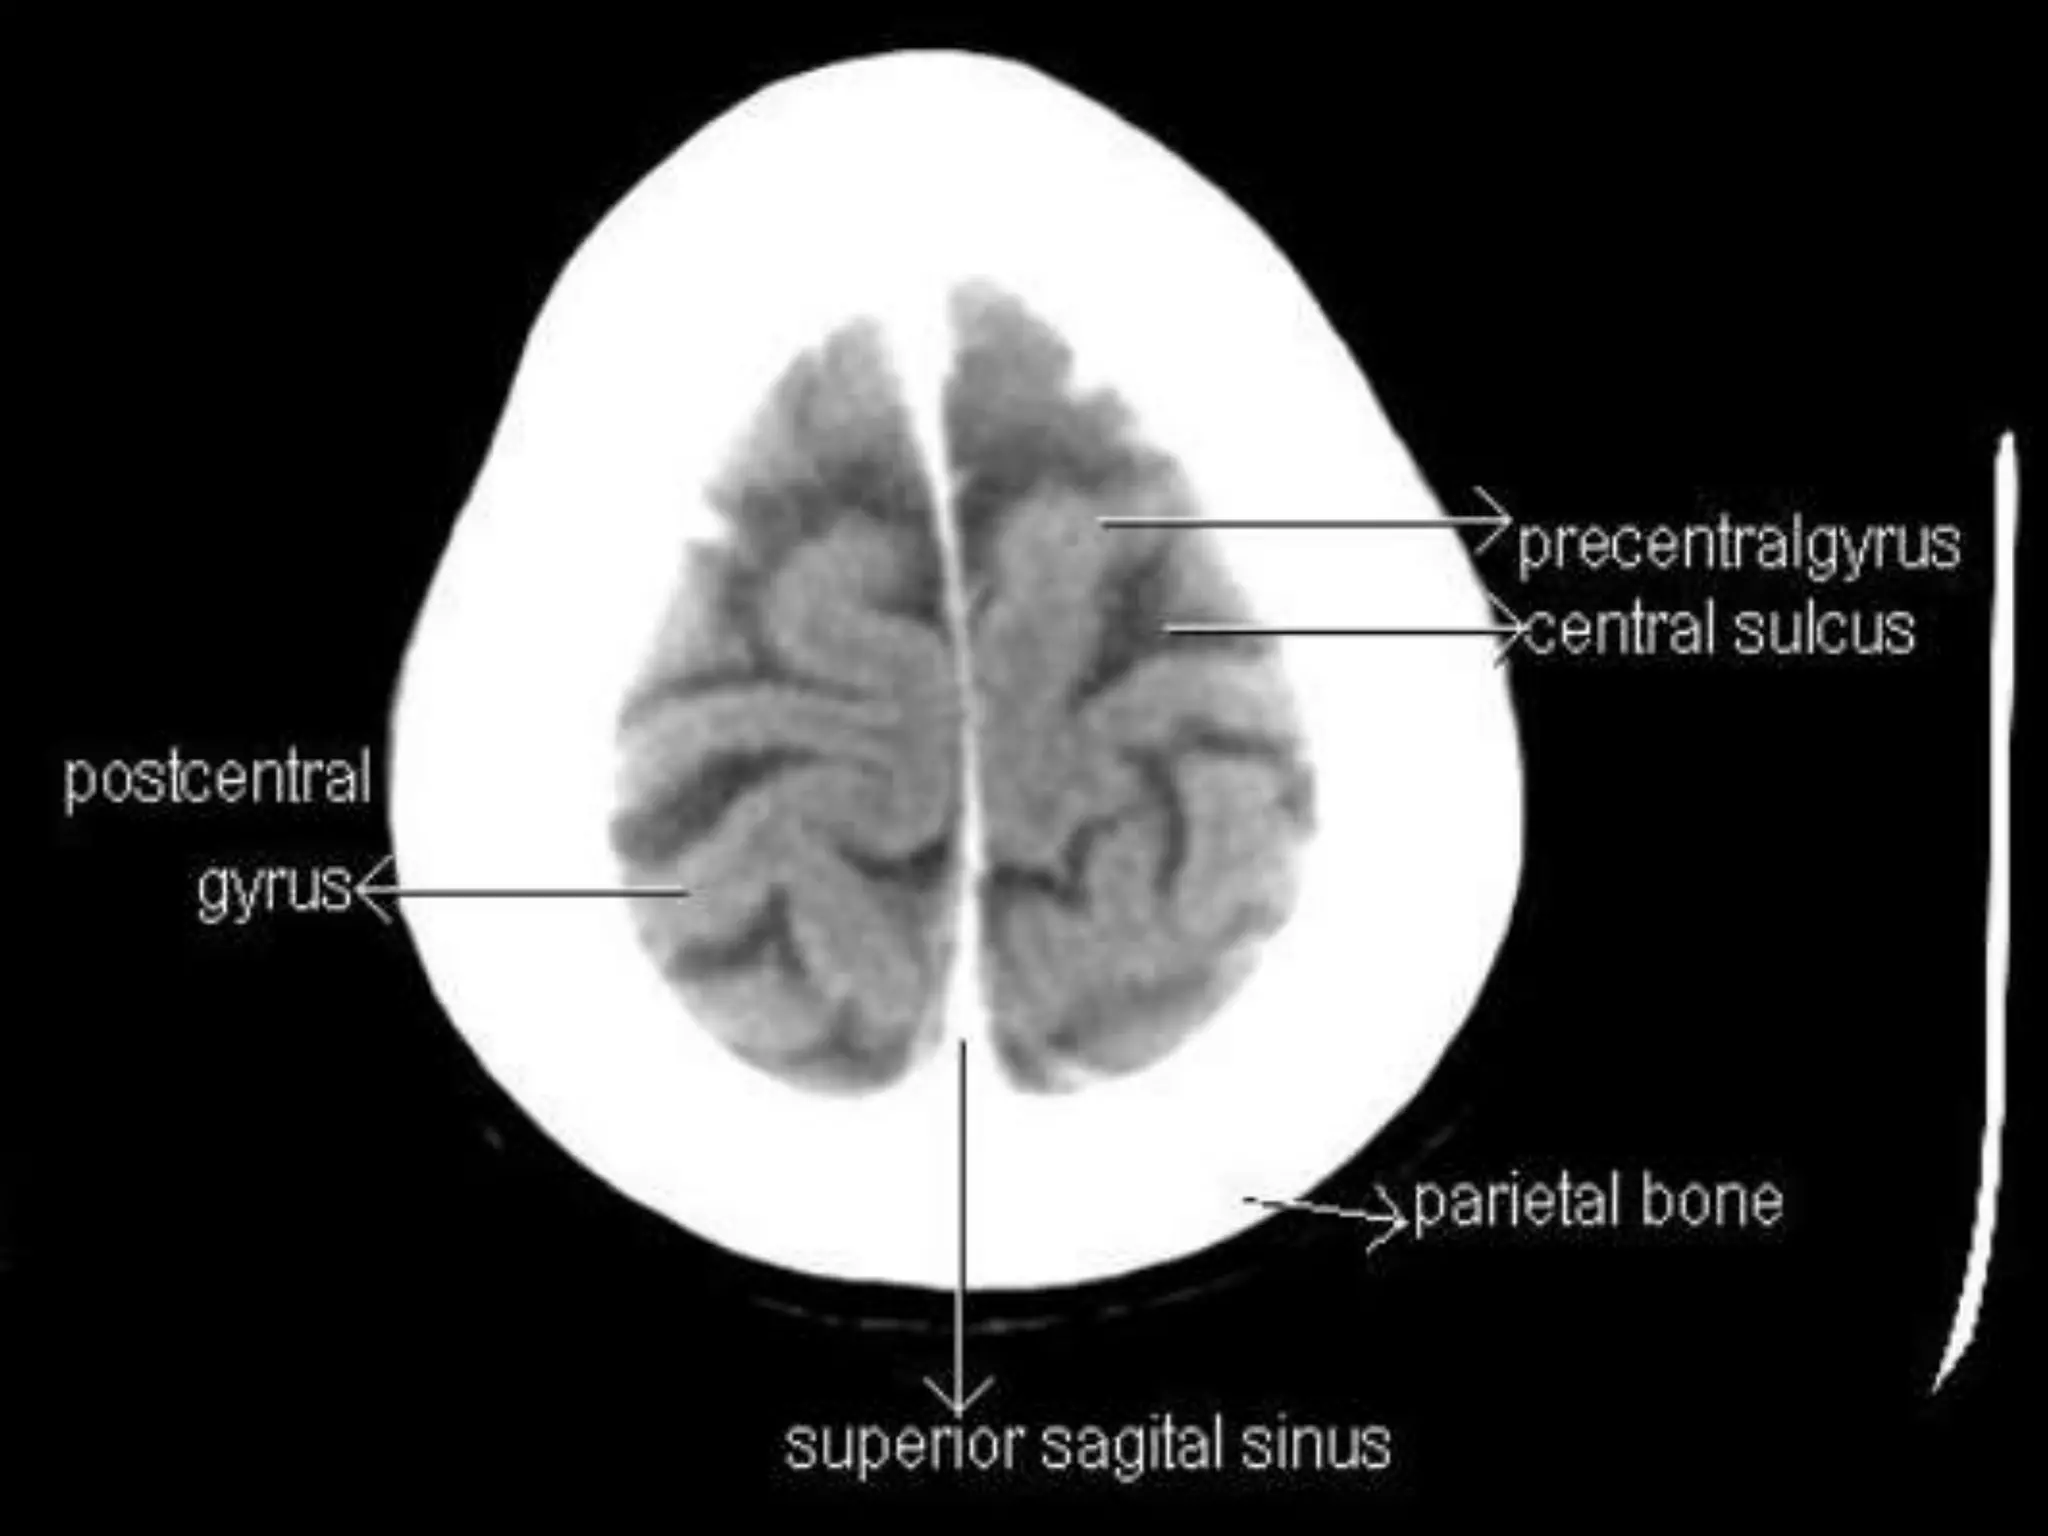

The two cerebral hemispheres are separated by

interhemispheric fissures and falx cerebri. On the lateral surface of the

brain, the sylvian fissure (lateral fissure) and the rolandic fissure (central

fissure) separate the cerebral hemisphere into the frontal lobe, temporal

lobe, parietal lobe, and a line drawn from the parieto-occipital sulcus

onto the preoccipital notch, delineating the boundaries of the parietal

and temporal lobes from that of the occipital lobe.

The frontal lobe, the largest of all the brain, has four principal

gyri: the precentral gyrus and the superior frontal, middle frontal, and

inferior frontal gyri. The precentral gyrus, parallel to the central sulcus,

together with the anterior bank of the central sulcus, comprises the

primary motor area, which is one of the most important cortical areas

for movement. Rostral to the precentral sulcus is the premotor area,

another important area for movement. The middle frontal gyrus contains

Brodmann’s area 8, known as the frontal eye field, which is important for

conjugate eye movements. Another important motor area for speech

called Broca’s area, is located at the triangular and the opercular parts of

the inferior frontal gyrus in the dominant hemisphere.

In the parietal lobe, there are a postcentral gyrus, a superior

parietal lobule, and an inferior parietal lobule. The postcentral gyrus

is a primary somesthetic area involved in general body sensation.